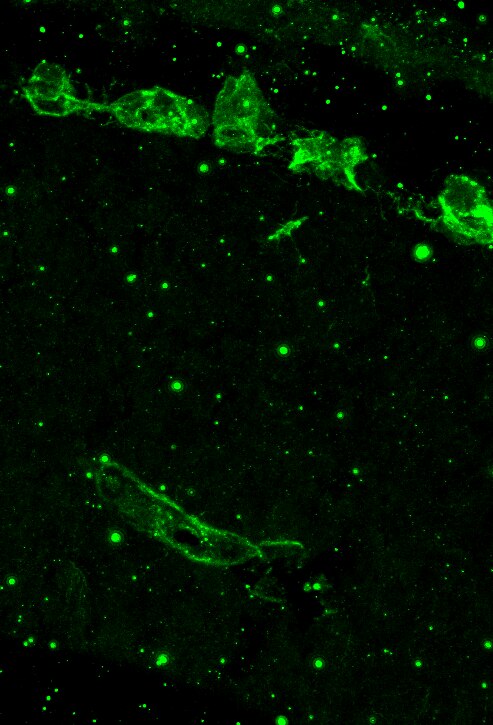

Enlarge |

Immunofluorescence -Frozen tissue sections | Mouse | 04/28/2020 |

IF | Mouse | 01/09/2015 |

| Application: | Immunofluorescence -Frozen tissue sections | |

| Species: | Mouse |

| Application: | IF | |

| Species: | Mouse |